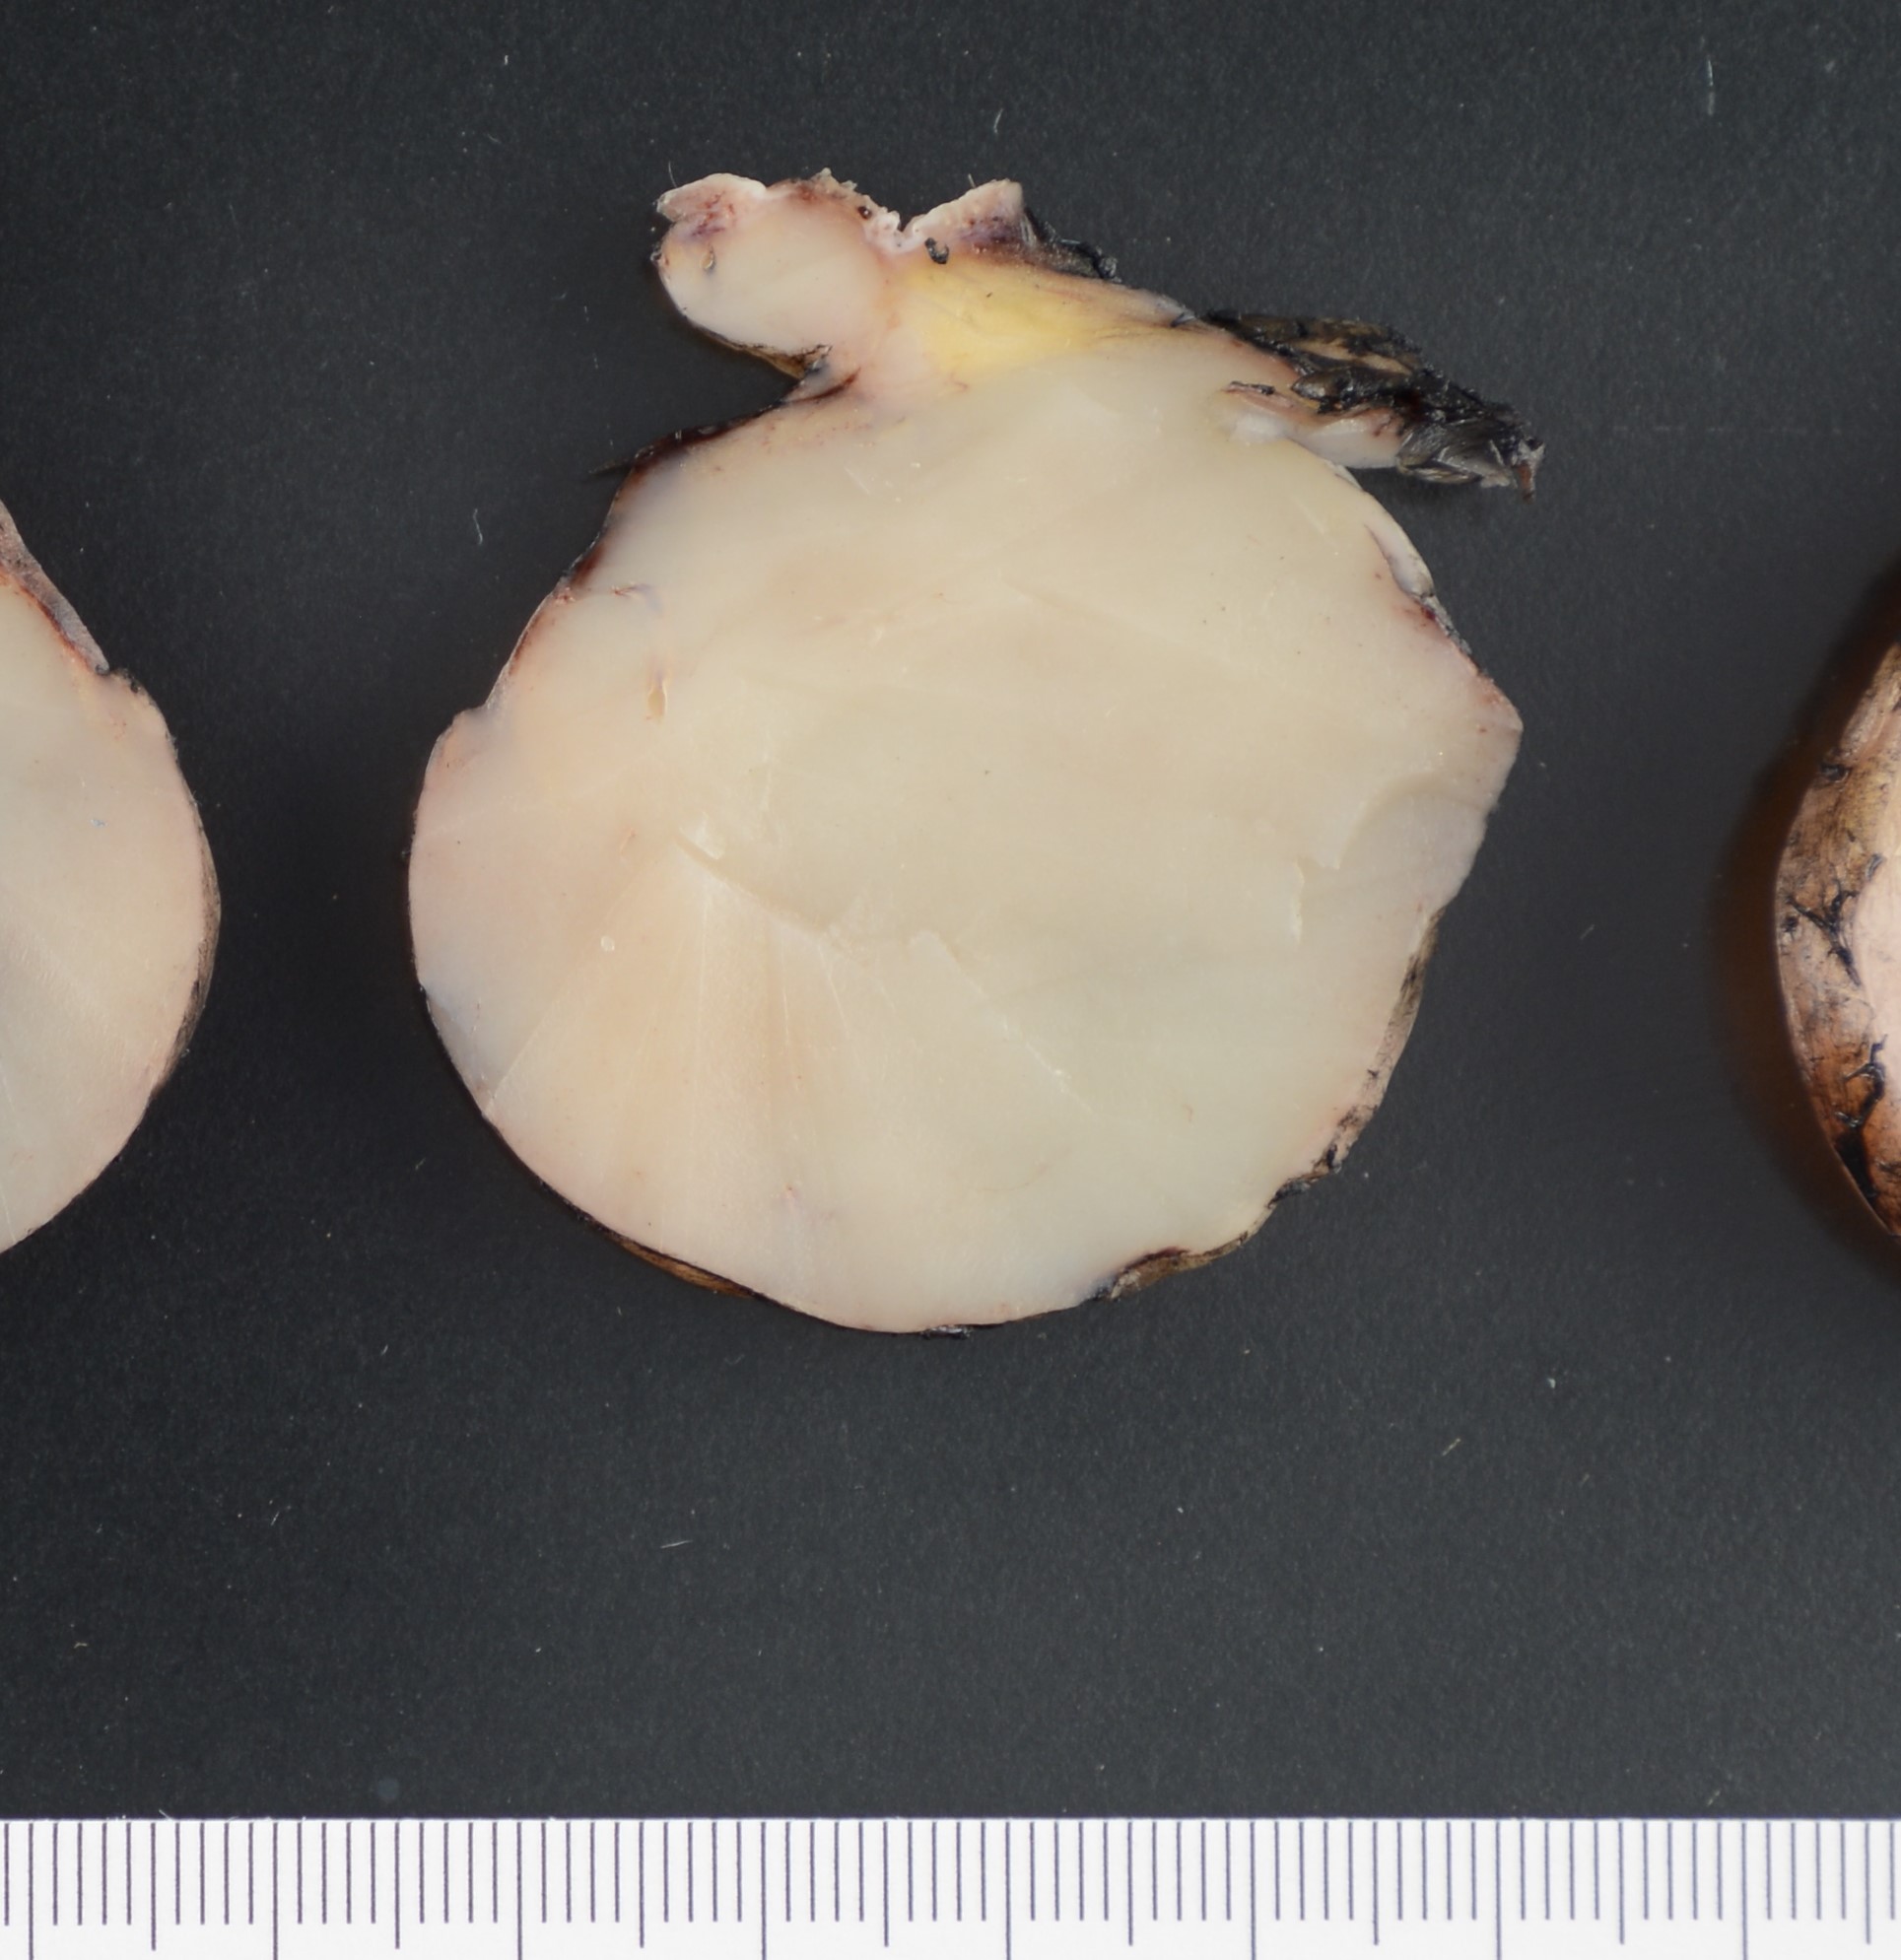

In early stage DFSP forms as a firm plaque-like lesion that grows slowly and later becomes nodular, hence “protuberant”. Most DFSP are biopsied during the nodular stage, consisting of a solitary-protuberant gray-mass involving subcutis and skin. Some tumors may be centered in the subcutaneous soft tissue with subtle dermal involvement. Therefore, involvement of the dermis may not always be evident in the initial biopsy, as seen in the present case.